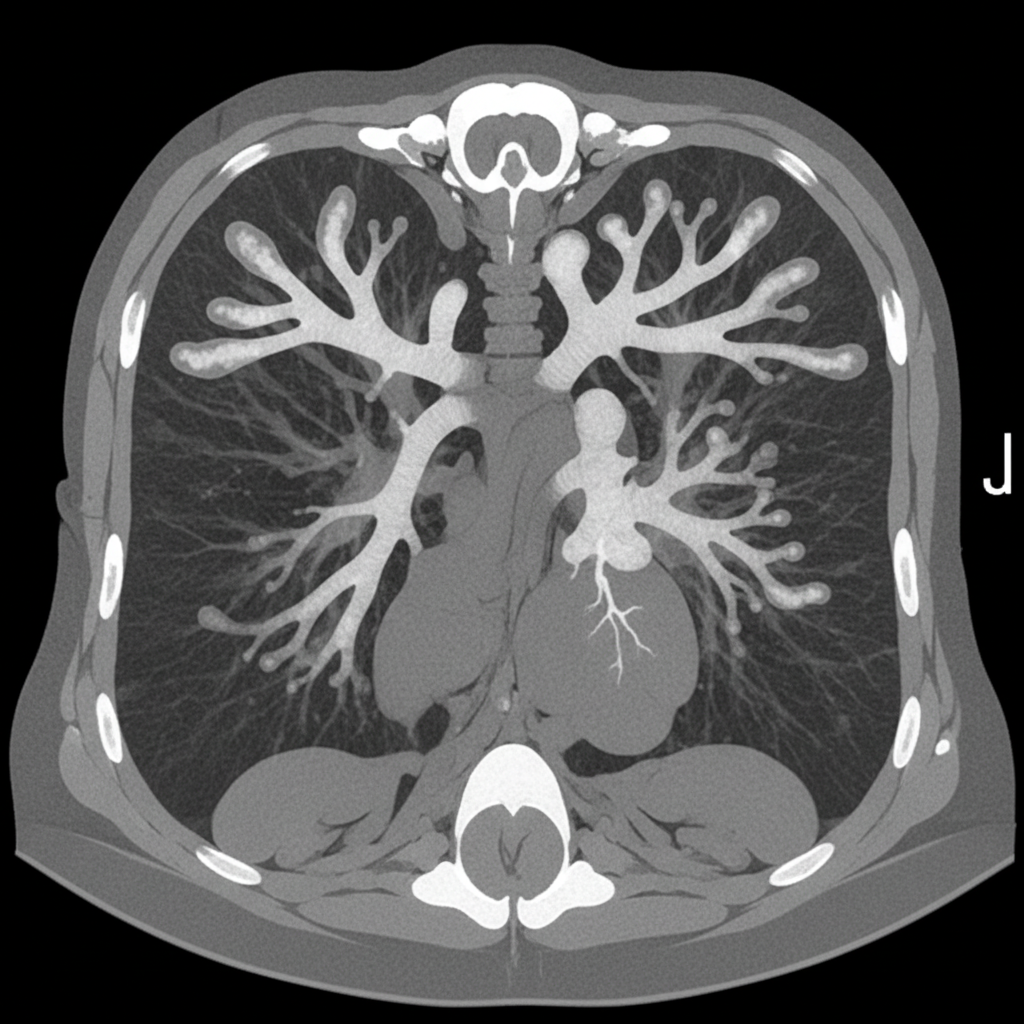

An asthmatic presents with brownish plugs in sputum. CT chest was performed. What is the diagnosis?

Explanation: ***Allergic Bronchopulmonary Aspergillosis (ABPA)*** - The CT chest demonstrates **central bronchiectasis with high-attenuation mucoid impaction** producing the classic **"finger-in-glove" sign** — pathognomonic for ABPA - The clinical triad of **asthma + brownish mucus plugs (containing fungal hyphae of *Aspergillus fumigatus*) + central bronchiectasis on CT** is diagnostic - Additional CT features include **bronchial wall thickening**, mosaic attenuation, and air trapping peripherally - ABPA results from a **Type I and Type III hypersensitivity reaction** to *Aspergillus fumigatus* colonizing the airways of asthmatics and cystic fibrosis patients *Aspergilloma* - Aspergilloma (mycetoma) presents as a **fungal ball within a pre-existing pulmonary cavity** with the "Monod sign" (air crescent sign) on CT - It typically occurs in patients with **structural lung disease** (old TB cavities, bronchiectasis) and does NOT cause central bronchiectasis with mucoid impaction - Clinical: hemoptysis is the hallmark, NOT mucus plugs in an asthmatic *Pulmonary Tuberculosis* - TB on CT shows **upper lobe consolidation, tree-in-bud nodularity, cavitation**, and lymphadenopathy - Does NOT produce central bronchiectasis with mucoid impaction or the finger-in-glove pattern - Sputum would show **AFB**, not brownish mucus plugs from fungal colonization *Eosinophilic Pneumonia* - CT shows **bilateral peripheral consolidation** (reverse pulmonary edema pattern / "photographic negative of pulmonary edema") - Associated with peripheral blood eosinophilia and BAL eosinophilia - Does not produce mucoid impaction or central bronchiectasis; lacks the *Aspergillus* colonization component